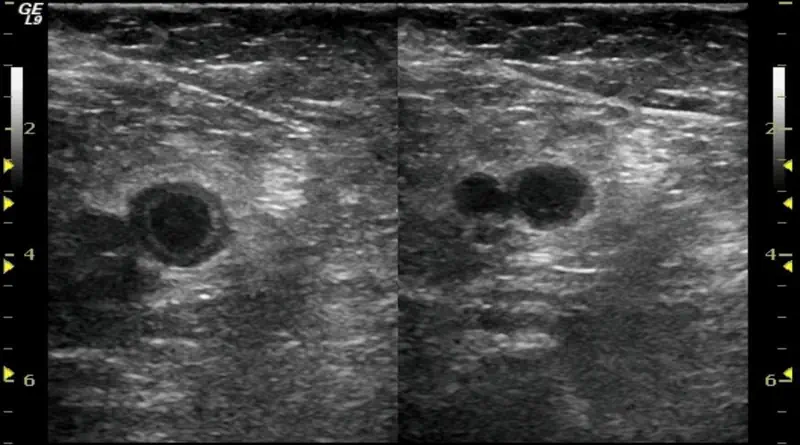

Ultrasound for Blood Clot Diagnosis

The main tool to diagnose a blood clot in a leg vein is ultrasound. The advantages of ultrasound are that it is accurate, safe, cheap and available almost everywhere.

There are three signs of clots that we can identify with ultrasound:

- Visible clot. Basically, this is when we can see the clot. But often we cannot actually see the clot. It is practically invisible on ultrasound.

- Lack of blood flow. Veins are supposed to move blood up toward the heart. But if there is a blood clot in the vein, blood might not be able to flow freely. It is important to remember that some clots do not block flow completely. So even if we can detect blood flow, this does not mean there is nothing in the vein.

- Non-compressible veins. This is the most important finding. Veins are supposed to collapse when we press on them. But if there is clot in the vein, we will not be able to compress the vein. So even if we cannot see the clot, we will know it is there.